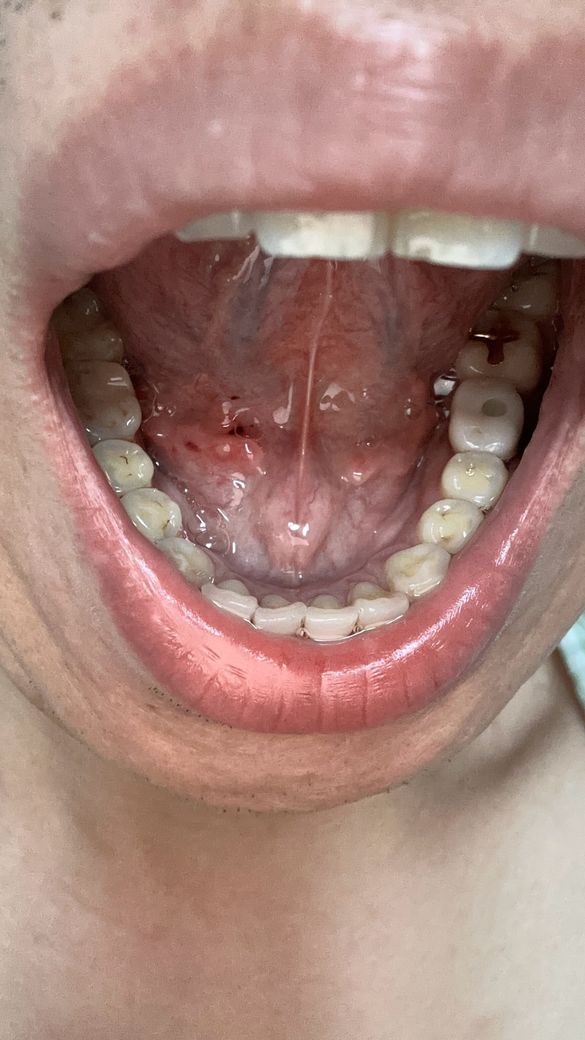

양치하다가 칫솔로 눌렀는데 피나는거처럼 됬어요

빨갛게 된부분이 있는것같고 그래서 이거 병원가봐야되는지 그냥 냅둬도 괜찮음지 궁금해요 어떻게하는게 좋을까요?? 병원은 무슨과인가요?

• 2번 째 사진

양치 중 칫솔로 인해 잇몸이 붉어지고 피가 나는 것은 잇몸 염증의 초기 증상일 수 있습니다. 칫솔질 시 잇몸에 과도한 힘이 가해지거나, 치석이나 치태가 쌓여 잇몸이 자극받았을 가능성이 있습니다. 우선 2~3일 정도는 부드러운 칫솔모를 사용하여 잇몸에 자극을 최소화하고, 치실이나 치간칫솔을 사용하여 꼼꼼하게 치아 사이를 청결하게 관리해주세요.

만약 며칠 후에도 증상이 호전되지 않거나, 붓기나 통증이 심해진다면 치과에 방문하여 정확한 진단을 받아보는 것이 좋습니다. 치과에서는 잇몸 상태를 확인하고 필요한 경우 스케일링이나 다른 치료를 통해 잇몸 건강을 회복할 수 있습니다.